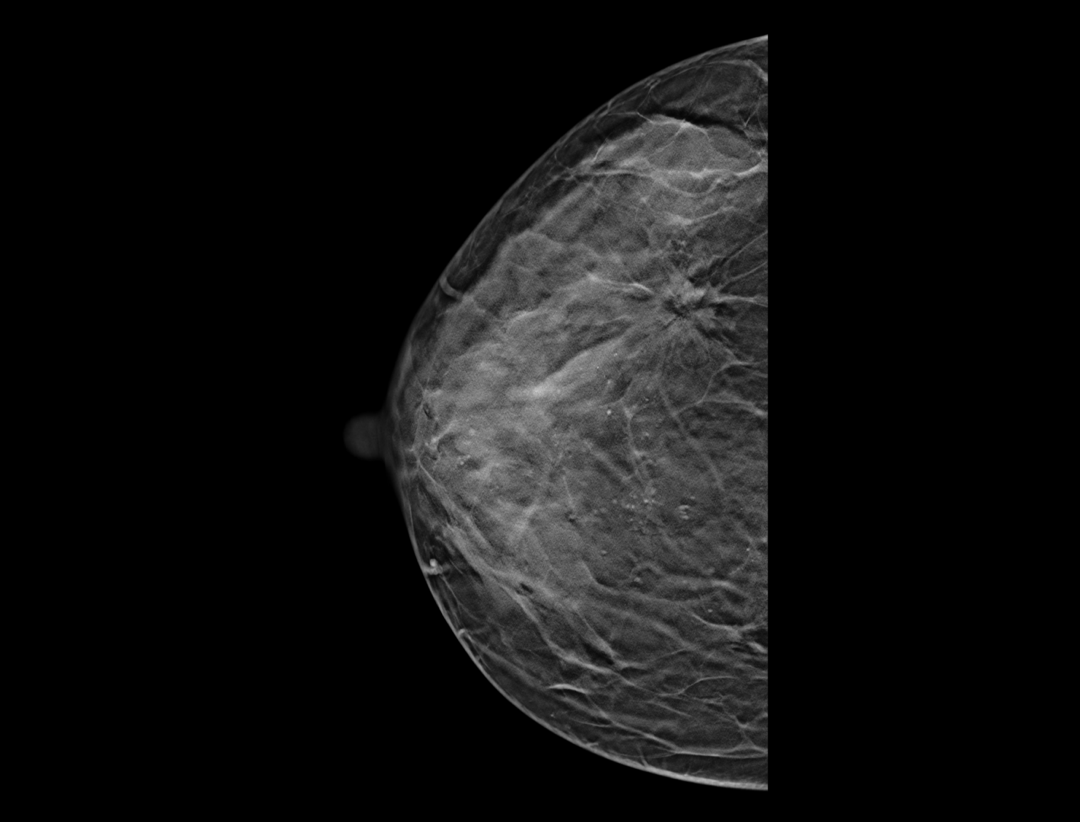

自定义层厚融合

更精细观察肿块及钙化簇的空间分布。